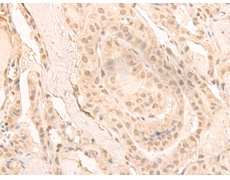

IHC positive control: |

Human cervical cancer |

IHC Recommend dilution: |

30-150 |